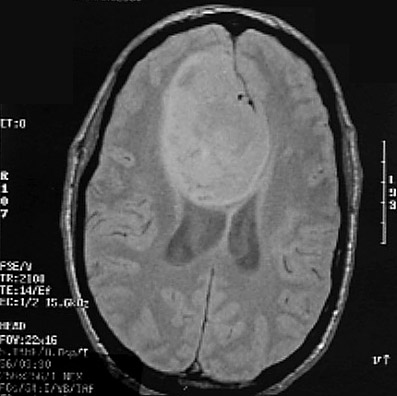

Click on the glioma in the MRI scan above:

This is an axial MRI scan demonstrating a large glioma impinging upon the ventricular system.